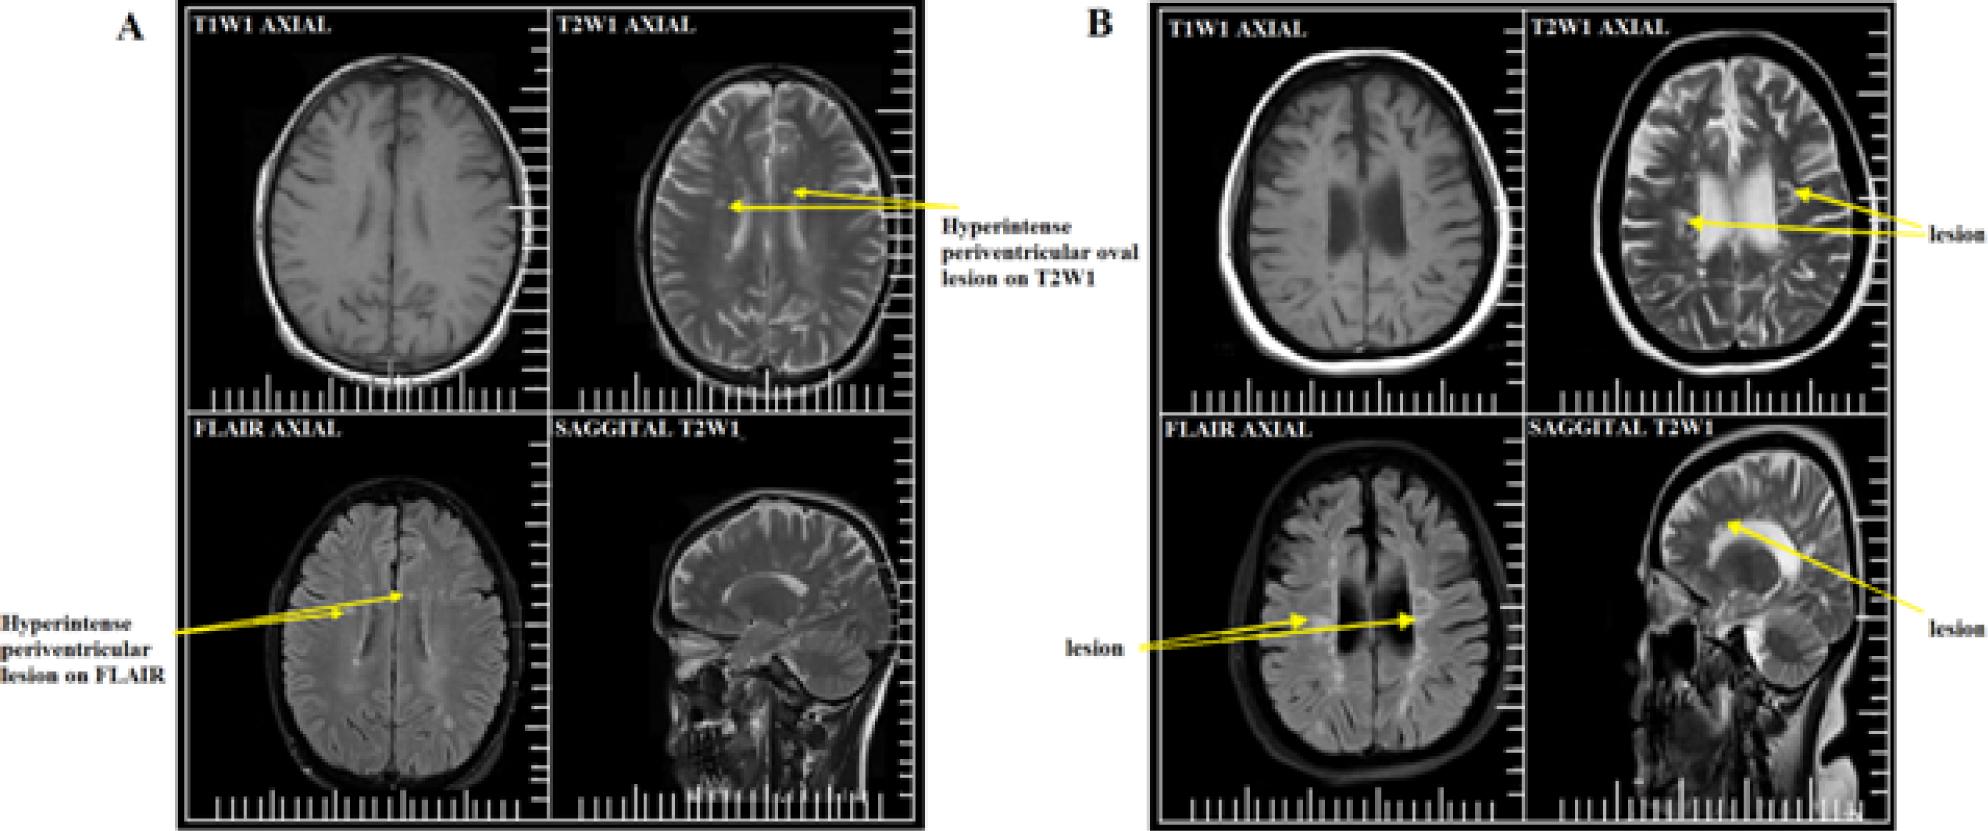

T2W sequences were more sensitive than T1W sequences for detecting MS lesions on MRI. T2W imaging sequences identified 99% patients with MS lesions (Figure 1; Table 4) compared with 47% on T1WI (Figure 1; Table 4). By contrast, FLAIR sequences were the most accurate, and 100% of the present cases of MS were detected using this (Figure 1; Table 4).

(A) A 29-year-old male patient: axial T1-weighted imaging (WI), T2WI, fluid-attenuated inversion recovery (FLAIR) imaging, and sagittal T2WI showing oval shaped white matter periventricular lesions; (B) a 38-year-old female patient: axial T1WI, T2WI, FLAIR, and sagittal T2WI showing oval shaped white matter periventricular lesions (Philips Achieva 1.5 T Nova Dual system)